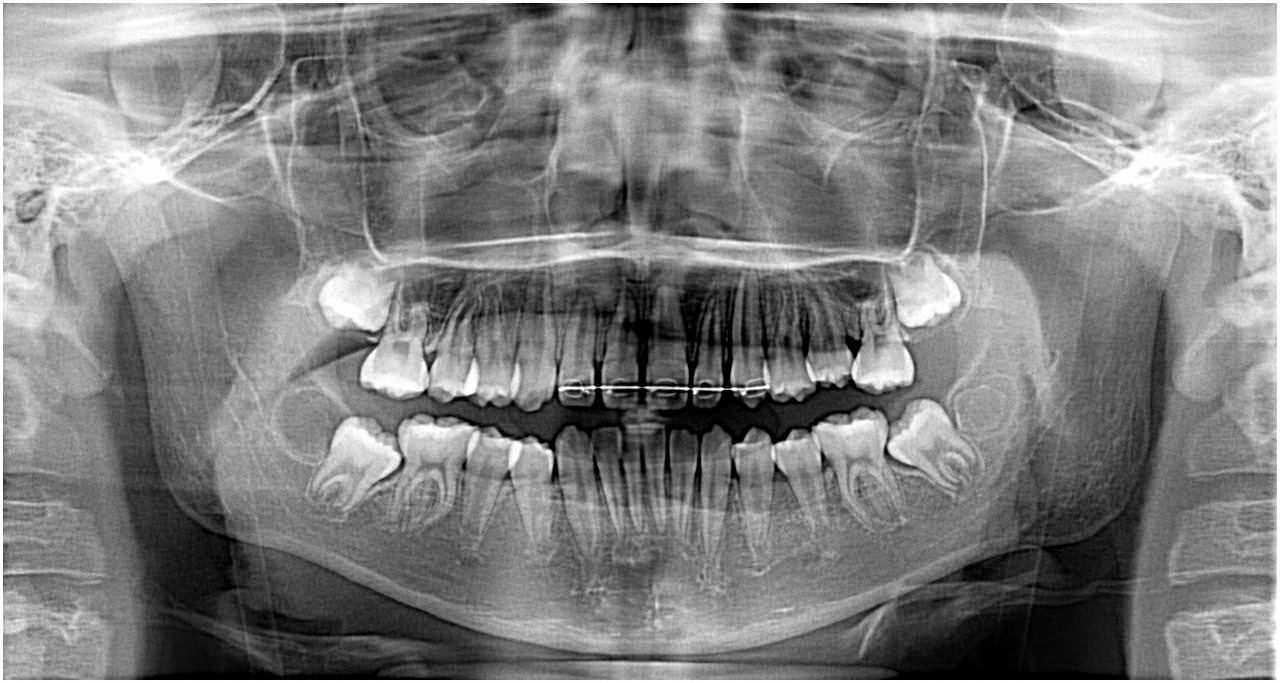

親不知を抜歯すると手前の歯が生えてきます。| |広島市安佐南区の歯科医院 親不知を抜歯すると手前の歯が生えてきます。 トップ お知らせ・ブログ 親不知を抜歯すると手前の歯が生えてきます。 親不知を抜歯すると手前の歯が生えてきます。 Web診療予約 初めての方へ 選ばれ続ける理由 院内設備について 歯が痛いしみる一般歯科 歯がぐらぐらする歯周病 健康な歯を保ちたい予防歯科 子供の虫歯予防をしたい小児歯科 銀歯をセラミックに審美歯科 白い歯を目指しませんか?ホワイトニング 矯正専門医がいるので安心矯正歯科 抜けた歯を補いたいインプラント・入れ歯 医院案内 スタッフ紹介 メリィハウス歯科クリニックオフィシャルホームページ ラベンダー歯科クリニックオフィシャルホームページ お知らせ・ブログ ホーム 診療科目 一般歯科 歯周病治療 予防治療 小児歯科 審美治療 ホワイトニング 矯正歯科 入れ歯・インプラント マウスピース矯正 初めての方へ 院長・スタッフ 設備紹介 医院案内・アクセス メニューを閉じる